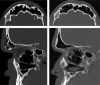

Management of frontal sinus fractures is controversial with no universally accepted treatment protocol. Goals of management are to correct aesthetic deformity, preserve sinus function when it is deemed salvageable, prevent sequela related to the injury, and minimize complications associated with intervention. Studies suggest that frontal sinus injuries, including disruption of the nasofrontal outflow tract (NFOT), can be managed nonoperatively in many cases. Advances in the utilization of endoscopic techniques have led to an evolution in management that reduces the need for open procedures, which have increased morbidity compared with endoscopic approaches. We employ a minimally disruptive protocol that treats the majority of fractures nonoperatively with serial clinical and radiographic examinations to assess for sinus aeration. Surgical intervention is reserved for the most severely displaced and comminuted posterior table fractures and unsalvageable NFOTs utilizing endoscopic approaches whenever possible.